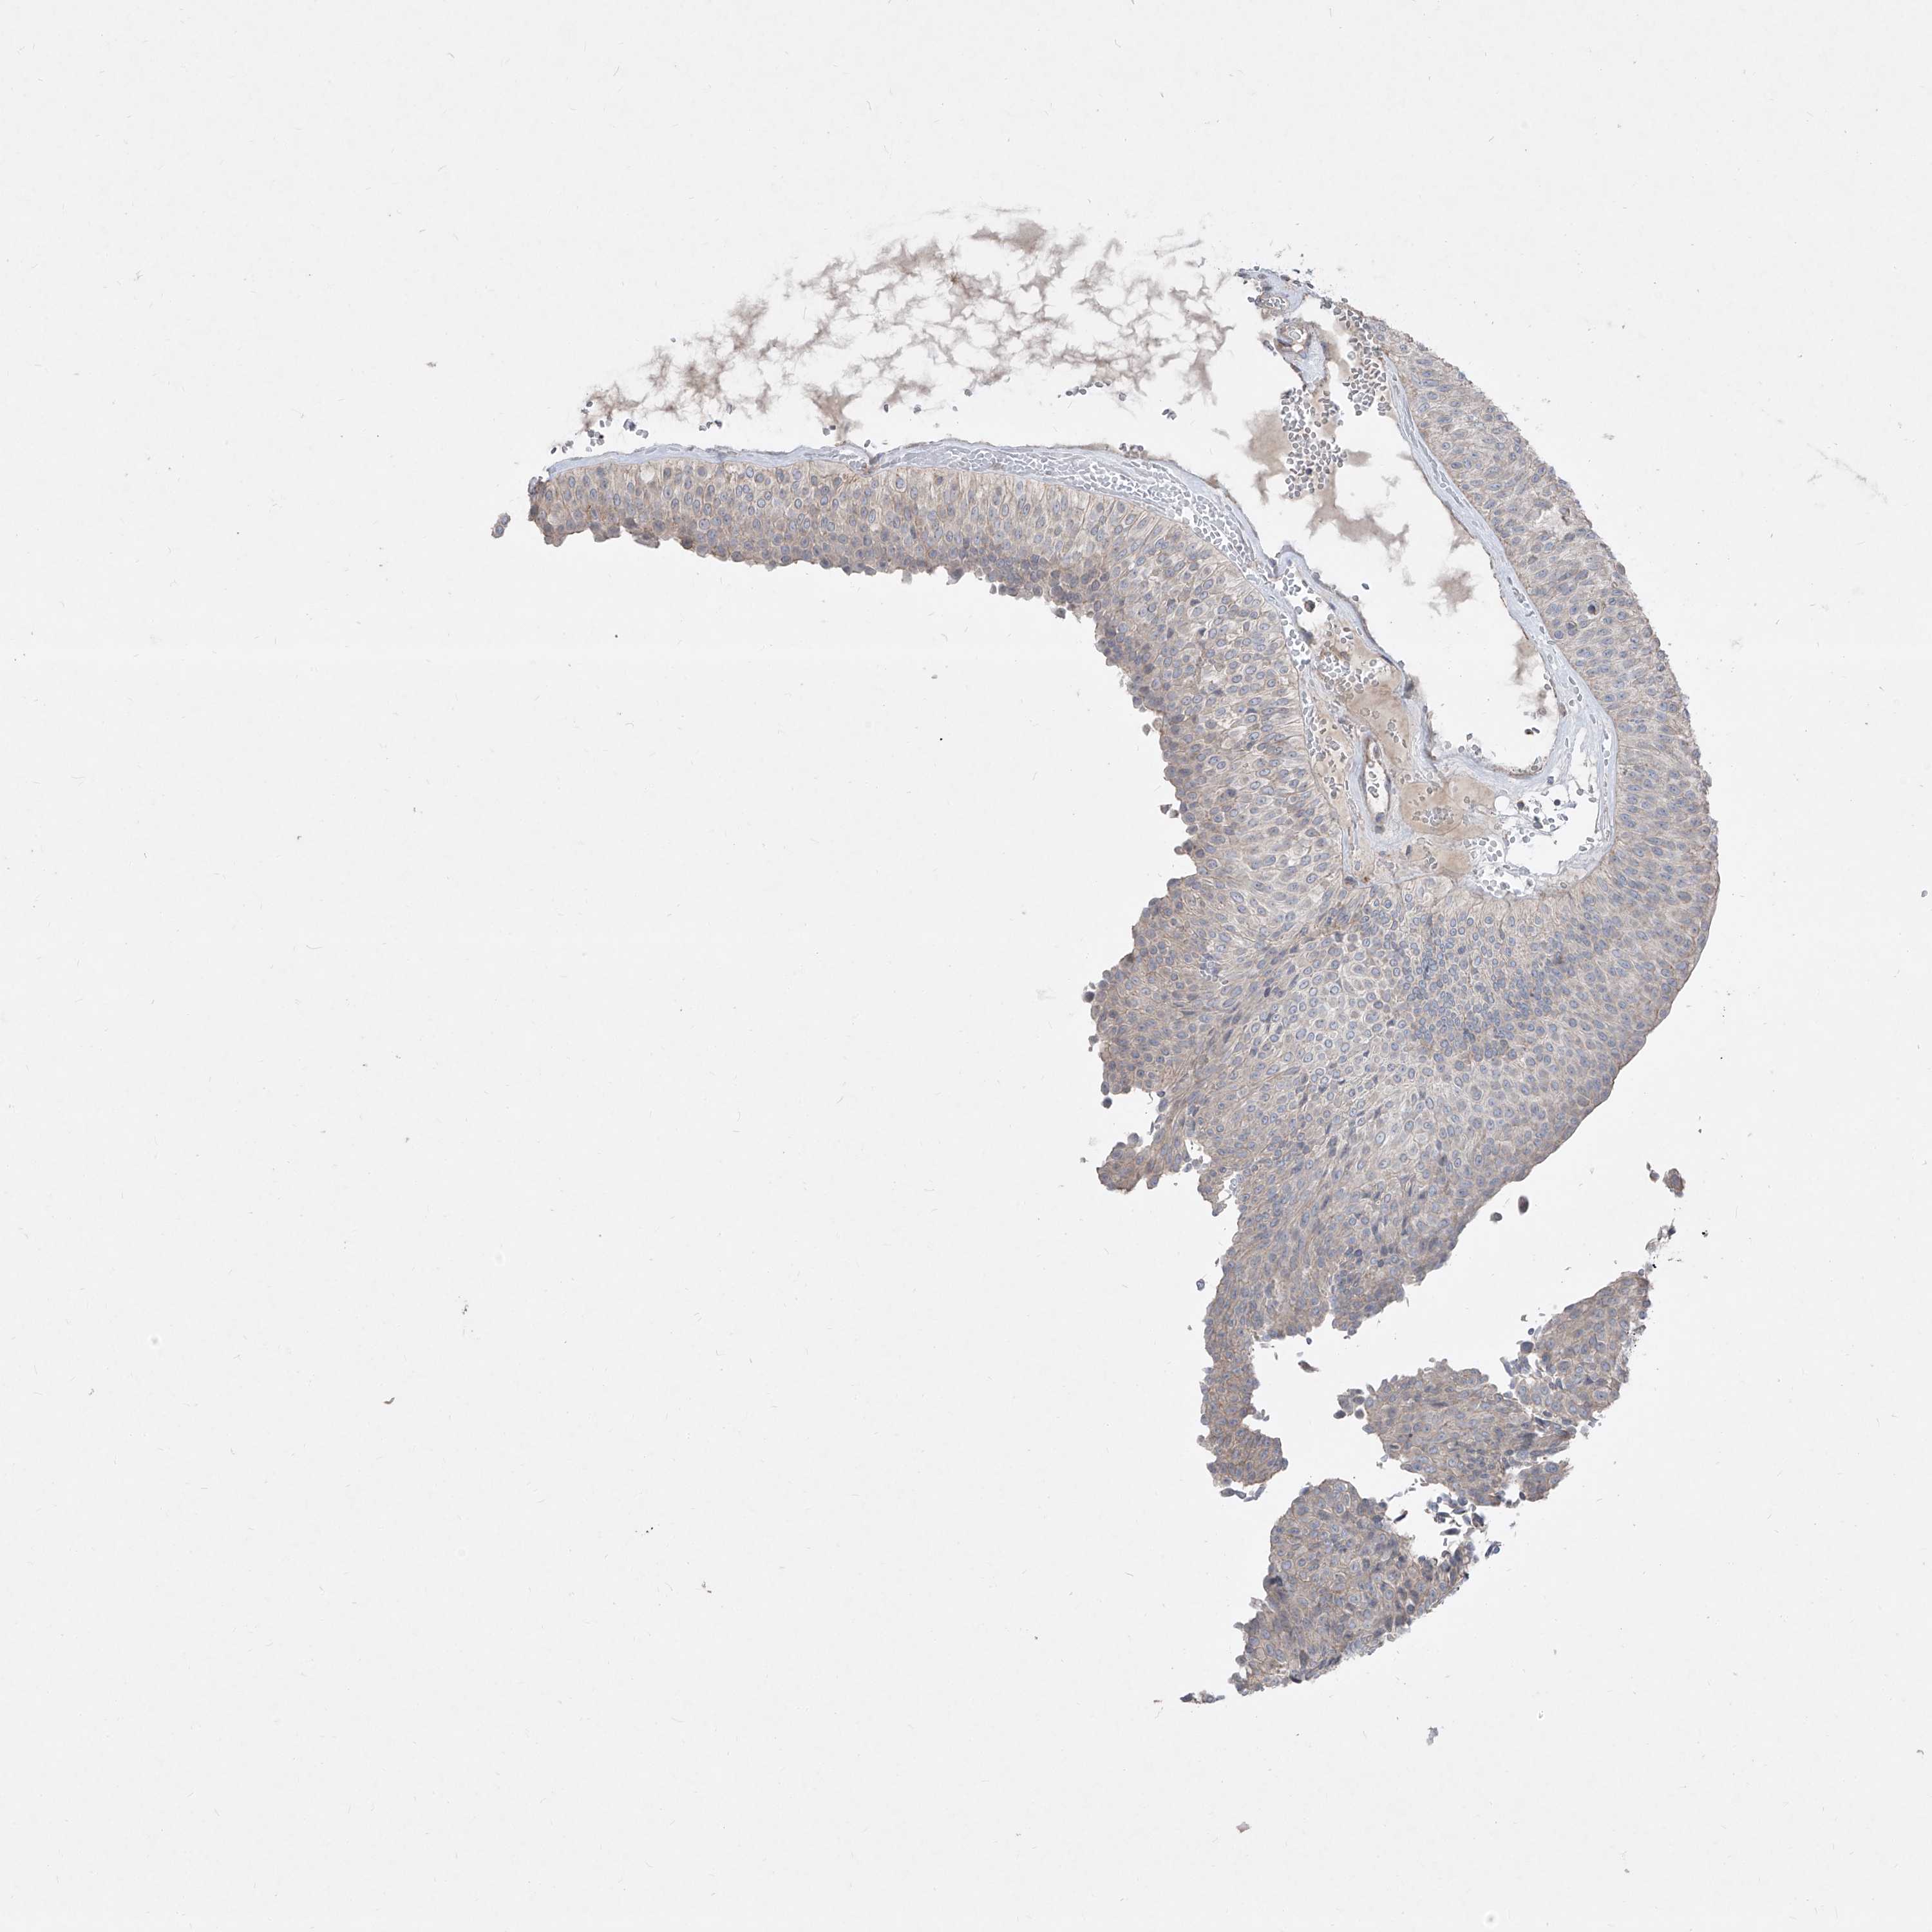

UROTHELIAL CANCER - Protein expressioni

A mouse-over function shows sample information and annotation data. Click on an image to view it in a full screen mode. Samples can be filtered based on level of antibody staining by selecting one or several of the following categories: high, medium, low and not detected. The assay and annotation is described here.

Antibody stainingi

Antibody staining in the annotated cell types in the current human tissue is reported as not detected, low, medium, or high, based on conventional immunohistochemistry profiling in selected tissues. This score is based on the combination of the staining intensity and fraction of stained cells.

Each image is clickable and will lead to virtual microscopy that enables deeper exploration of all samples and also displays staining intensity scores, fraction scores and subcellular localization as well as patient and tissue information for each sample.

Antibody HPA030287

Staining

High

Medium

Low

Not detected

Intensity

Strong

Moderate

Weak

Negative

Quantity

>75%

75%-25%

<25%

None

Location

Nuclear

Cytoplasmic/membranous

Cytoplasmic/membranous,nuclear

Urothelial carcinoma, High grade